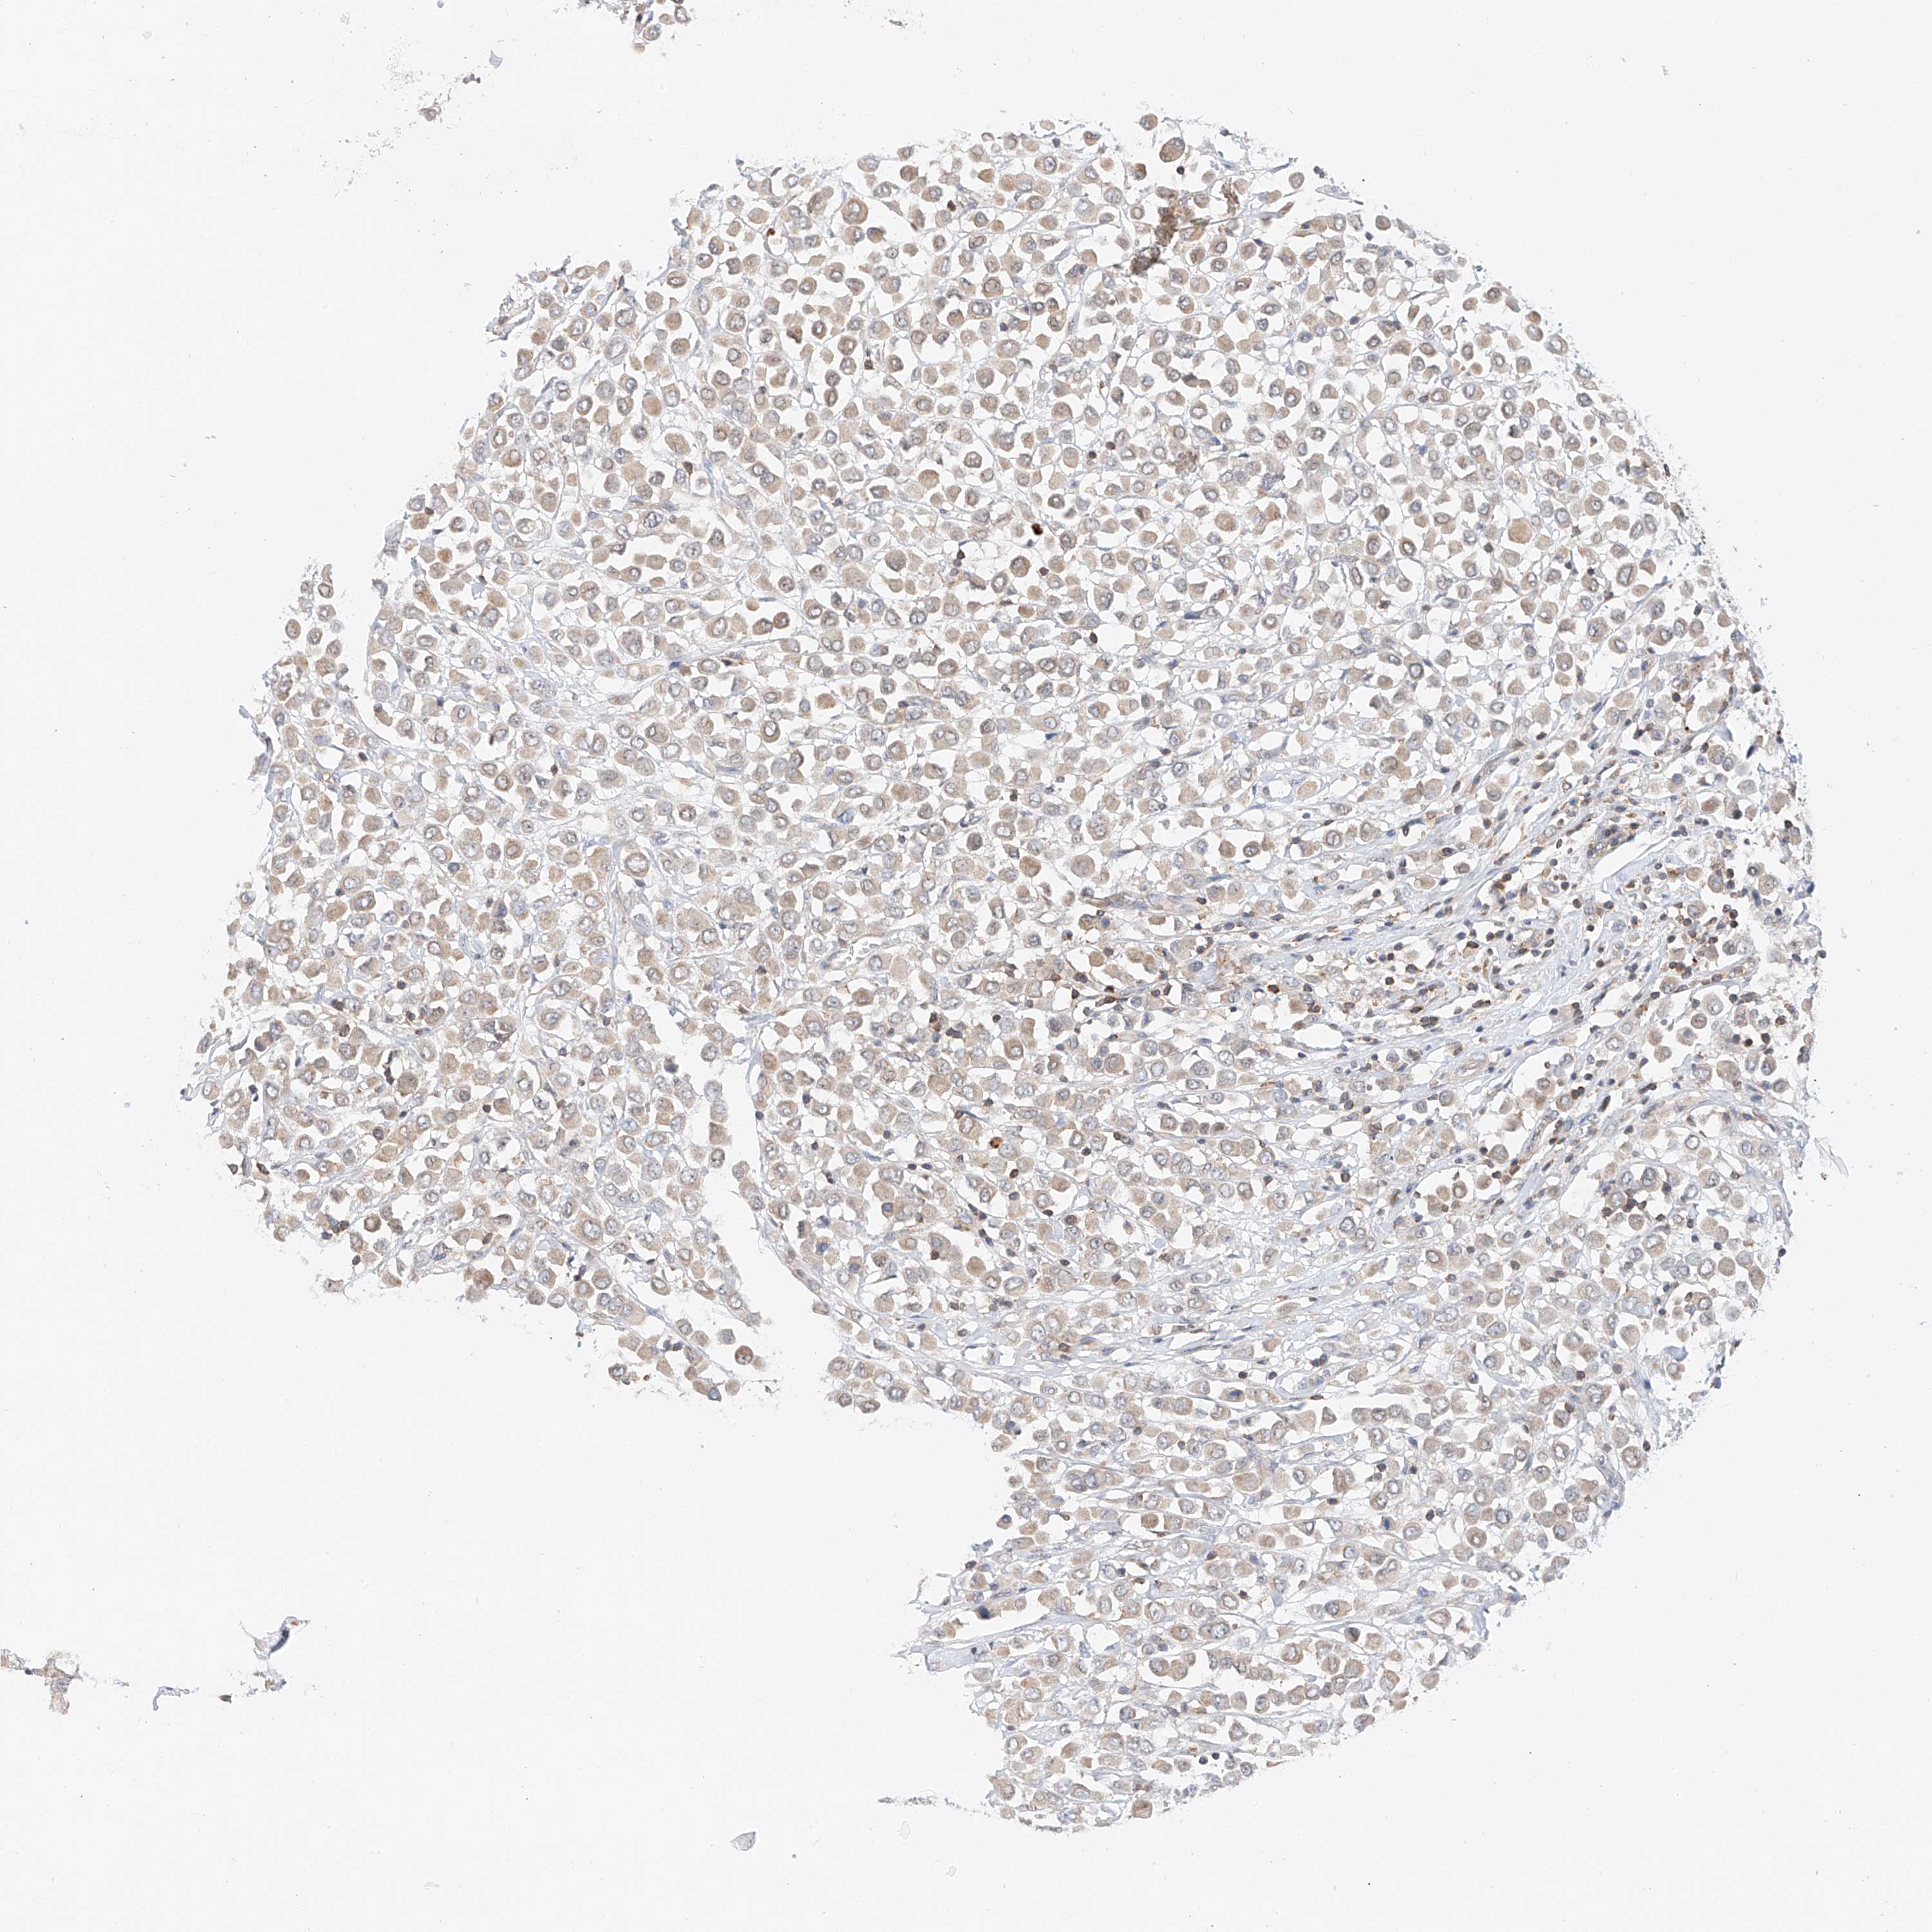

CANCER BREAST CANCER Show tissue menu

Breast cancer

Human cancer

MFN2 is not prognostic in Breast Invasive Carcinoma (TCGA)